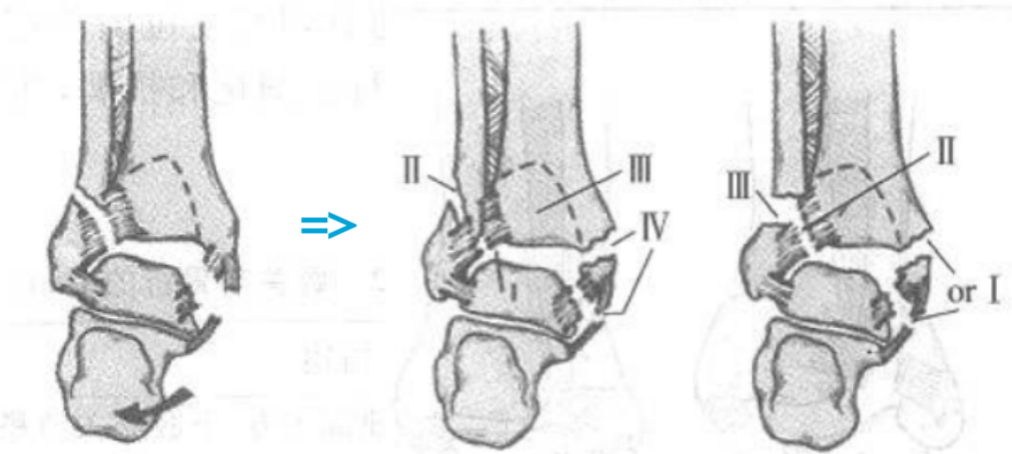

1、旋后(内翻)内收损伤(简称 SA)

损伤时,足呈旋后位,距骨内收,使踝关节外侧韧带紧张。

旋后内收损伤

Ⅰ度:首先发生的是外侧副韧带撕裂或者外踝的撕脱骨折,由于损伤发生于下胫腓联合远端,该韧带多保持完整。

I 度损伤 X 线显示:外踝间隙增宽,提示外侧副韧带撕裂,未见胫腓骨骨折,此型在 X 线上是隐匿的。

Ⅱ 度:内收的外力继续作用,内踝受内翻的距骨挤压作用,可造成内踝的垂直骨折,及胫骨远端关节面的内侧部分压缩骨折,如果合并其他方向的外力,有可能造成内踝的斜行骨折。

II 度损伤 X 线片显示:腓骨骨折在下胫腓联合水平以下,内踝垂直骨折;侧位 x 线片显示后踝无骨折。